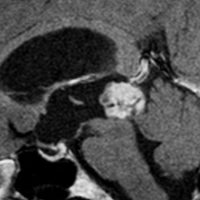

松果体細胞腫の例4(のう胞性腫瘍)

30代女性ののう胞性の松果体細胞腫です。これは大きな松果体嚢胞とほとんど画像では区別がつかないものでした。でも腫瘍ののう胞壁(液体の入っている袋の壁)の後方がガドリニウム増強されていてごく一部が実質性であることが解ります。